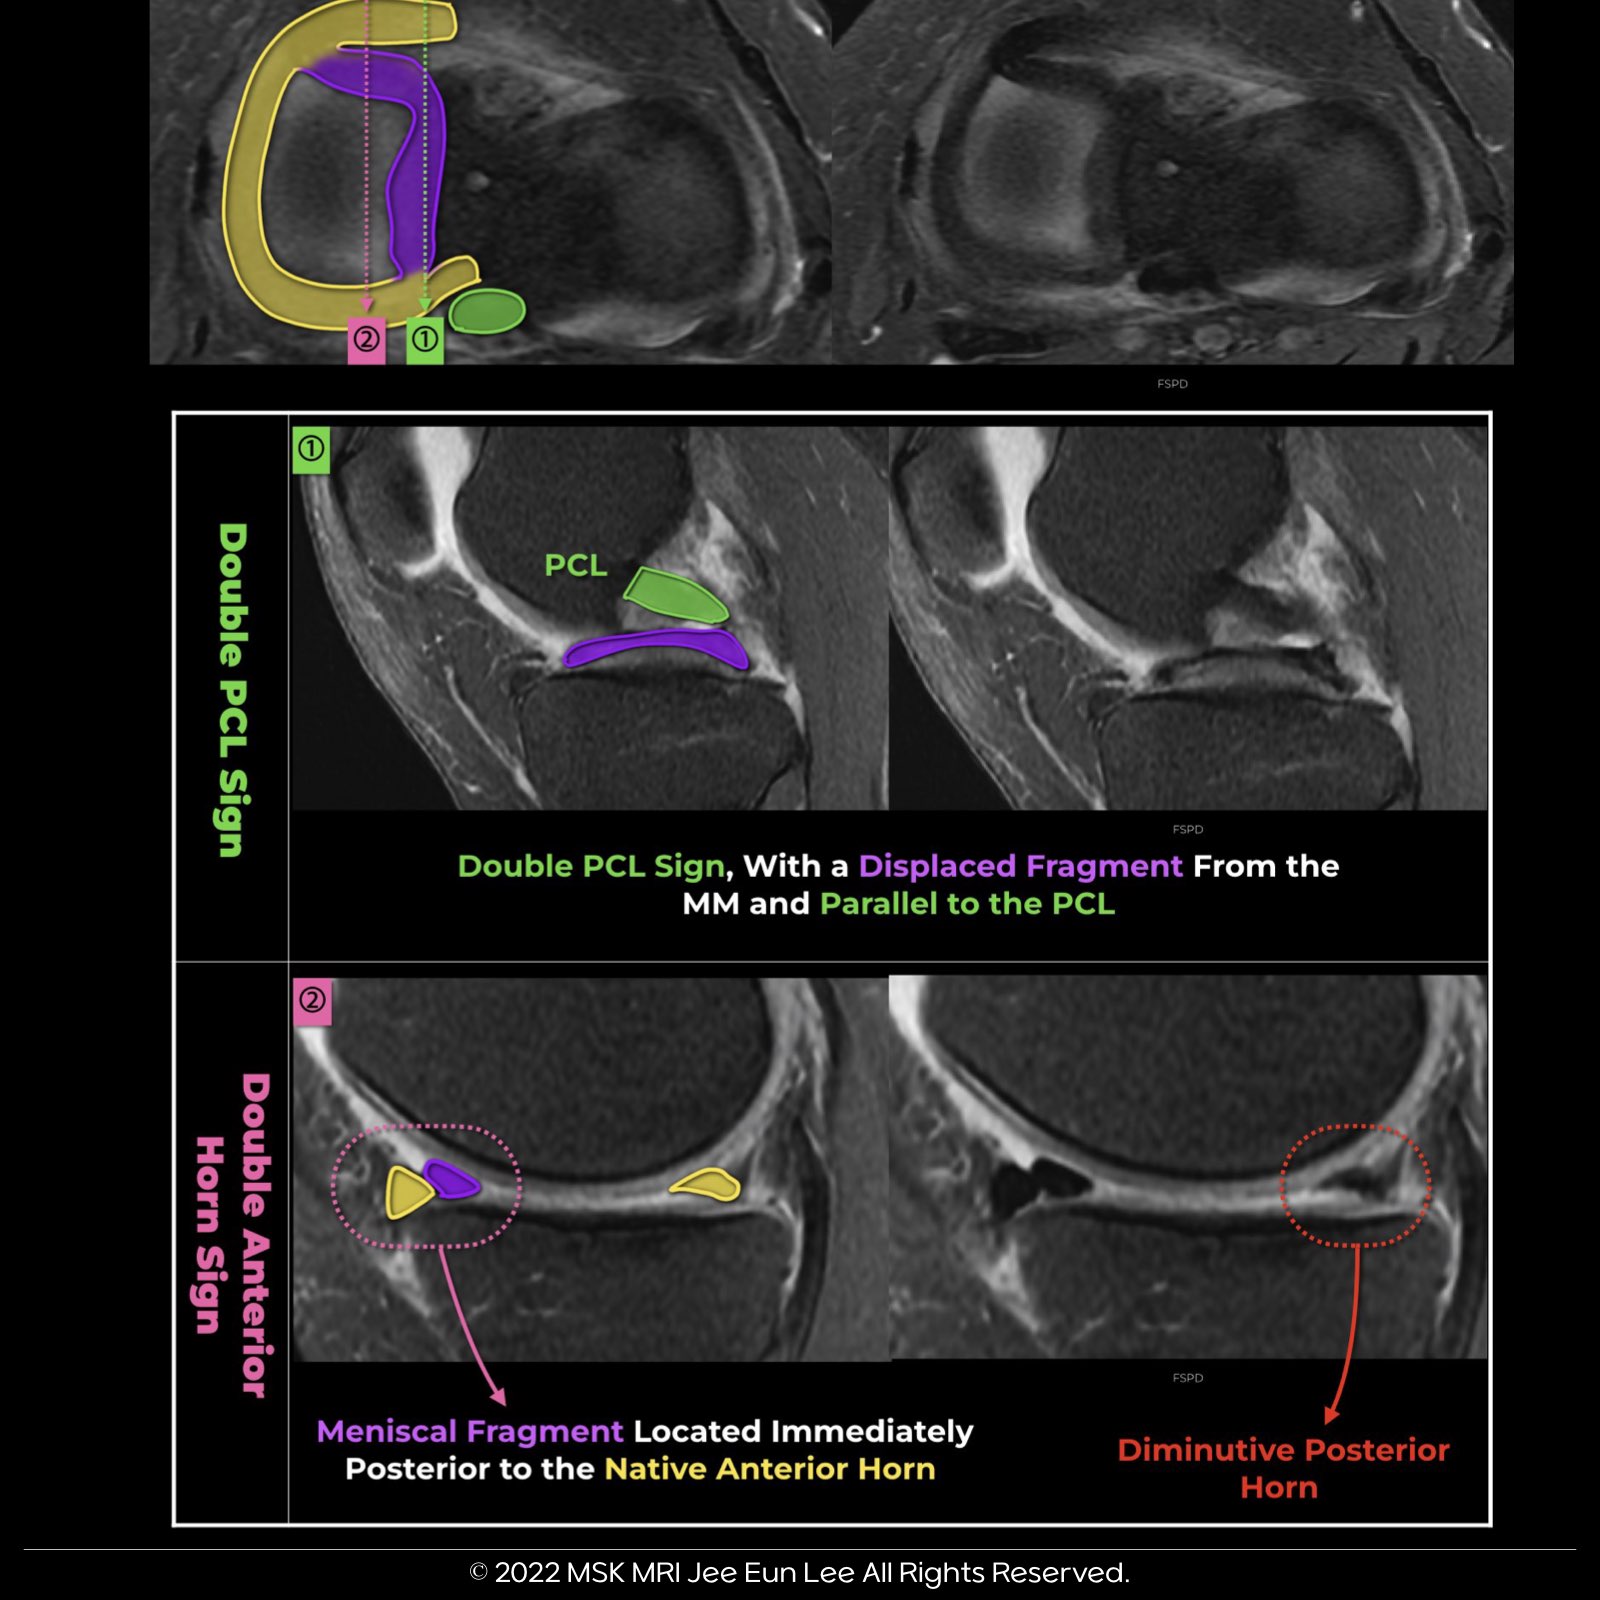

๐ง Double Posterior Cruciate Ligament (PCL) Sign:

Double posterior cruciate ligament (PCL) sign results from meniscal material in the notch, inferior and parallel to the PCL in the same sagittal plane.

๐งฉ Double Anterior Horn Sign:

The double anterior horn sign is presented as two adjacent triangular seemingly anterior horns on a sagittal image.

The anterior triangle represents the normal anterior horn, while the posterior triangle represents the displaced bucket handle segment.